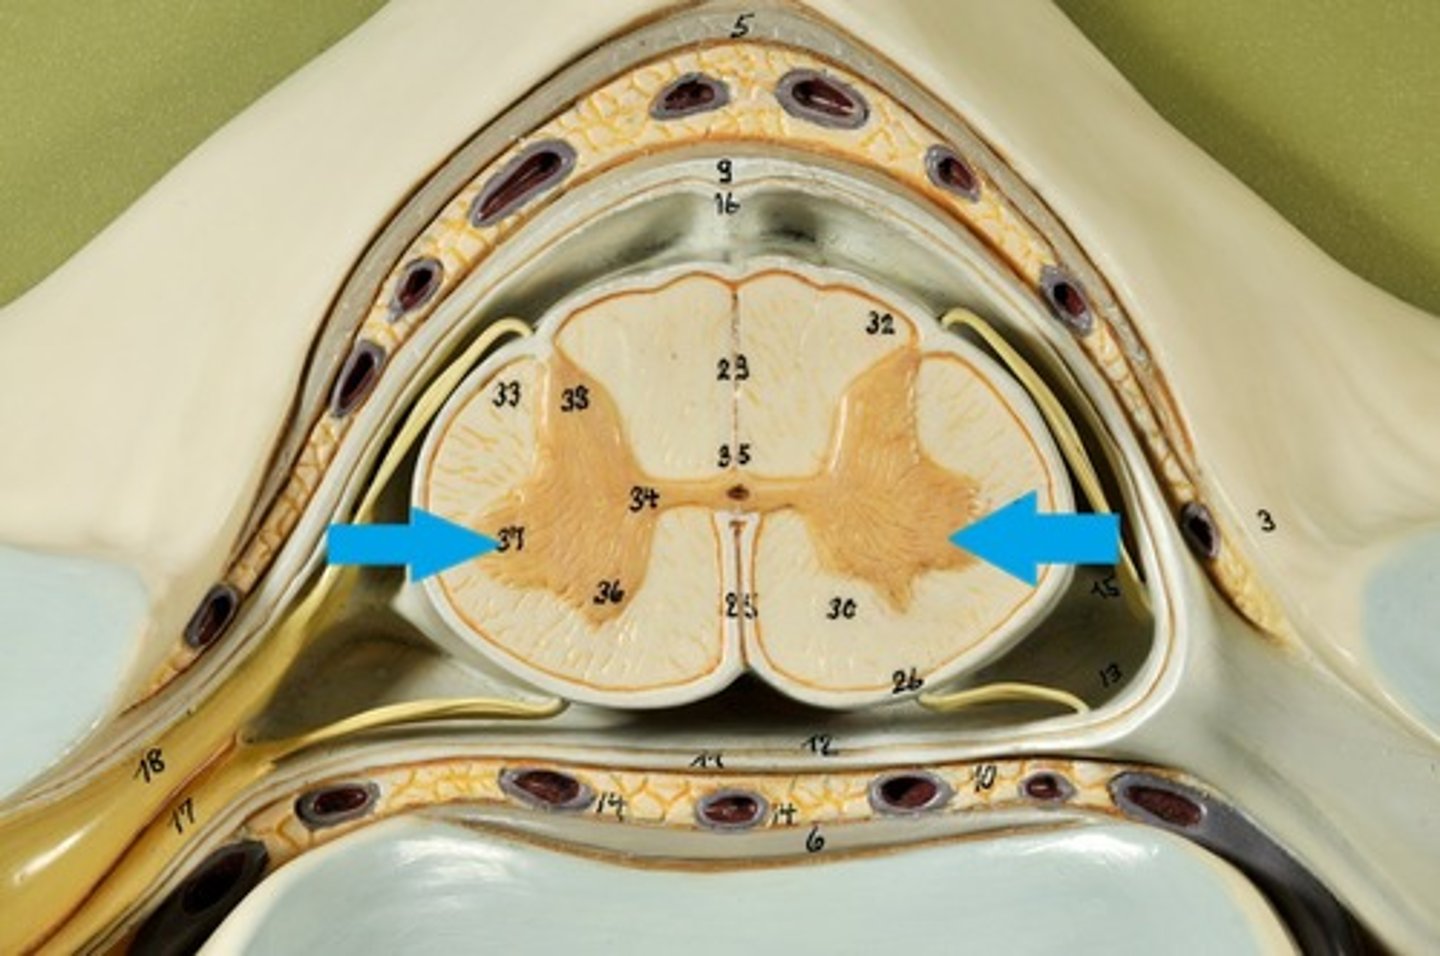

Spinal cord Anatomy (cross-sectional)

1)Internal butterfly shaped gray matter,

2)Exterior white matter,

3)Central canal filled with cerebrospinal fluid (CSF),

4)Cushioned & protected by meninges,

5)Pia mater,

6)Spinal nerves leave at the level of each vertenrae

Horns of Spinal Cord Anatomy

Dorsal Horns,

Ventral Horns,

Lateral Horns

Dorsal Horns

Lateral Horns

Ventral Horns

Interneurons

exterior white matter of the spinal cord

Ascending (sensory) and descending (motor) myelinated nerve tracts,

Posterior, anterior, lateral columns or funiculi

Posterior Columns

Anterior Columns

Lateral Columns/ funiculi

Central canal filled with what?

Central canal filled with cerebrospinal fluid (CSF)

Cushioned and protected by meninges

1) Cover the spinal cord

2) Dura mater, Arachnoid & Pia mater

dura mater of spinal cord

1) Separated from the periosteum by the epidermal space (fat, blood vessels)

2) Subdural space between dura and arachnoid mater

Dura Mater